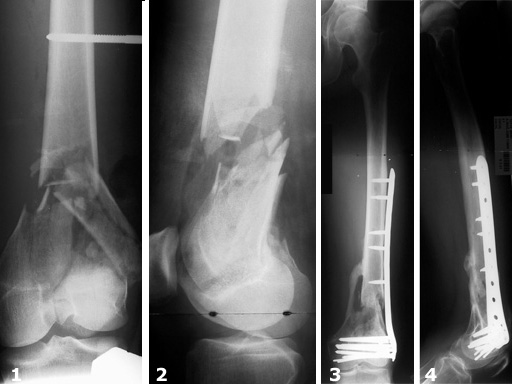

The LIS System Distal Femur (DF) is a new, fixed-angle implant system for the treatment of distal femoral fractures according to the principles of Minimally Invasive Surgery.

The criteria for inclusion were distal femoral shaft fractures and supracondylar and intraarticular femoral fractures of all degrees of severity. In this study, thirty-one distal femoral shaft fractures and eighty-five supracondylar and/or intraarticular femoral fractures were treated. There was a total of 45% (n=52) complex intraarticular fractures. With reference to the fractures treated, the follow-up rate was 93%. In 90% of the cases treated and followed up, fracture consolidation during the observation period could be confirmed.

The results of the study show that the new internal fixator is an excellent, safe procedure for the treatment of almost all fracture types, provided that thorough preoperative planning is performed and the surgeon has a sound knowledge of the operative technique. There is generally no need for primary cancellous bone grafting.